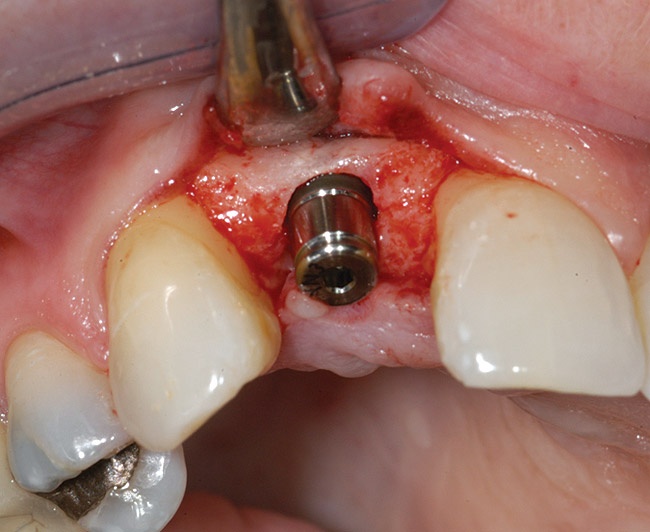

A 39-year-old woman presented with a failing endodontically treated maxillary right central incisor. Clinical and radiographic examination revealed a thick, flat periodontal biotype, high smile line, and a fistulous tract of the labial vestibule opposite the incisor (Figure 16 and Figure 17). Also noted post-extraction was a thin (< 2 mm) labial plate with 8 mm of vertical bone loss (Figure 18). Treatment consisted of a conservative flapless extraction with placement of a free connective tissue graft (Figure 19) sutured through the socket, along with placement of a bone mineralized allograft (MinerOss) (Figure 20 and Figure 21). Five months post-extraction, a root-form implant was placed, nonsubmerged, along with a bovine bone xenograft as a veneer into a sub-periosteal labial pouch (Figure 22 through Figure 24). A provisional crown was placed 3 months later, allowing for adequate soft-tissue grooming (Figure 25).

Figure 22  A thin labial plate (< 2 mm) at Stage I surgery.

Figure 22

Figure 23  Labial plate veneer graft with bovine hydroxyapatite.

Figure 23